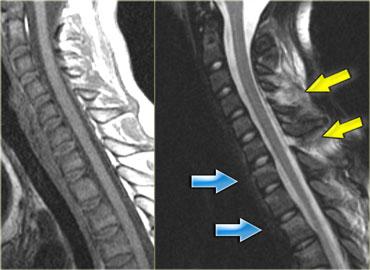

Tổn thương tủy sống trung tâm ở bệnh nhân chấn thương tăng duỗi trên nền thoái hóa và hẹp ống sống có sẵn.

Hội chứng tủy sống trung tâm (Central cord syndrome)

- Hội chứng tủy không hoàn toàn phổ biến nhất.

- Thường gặp ở người cao tuổi có thoái hóa cột sống nền hoặc người trẻ với chấn thương duỗi nặng (hình minh họa).

- Thiếu hụt vận động chi trên nặng hơn chi dưới, do bó vỏ-gai chi dưới nằm ở phần bên của tủy sống.